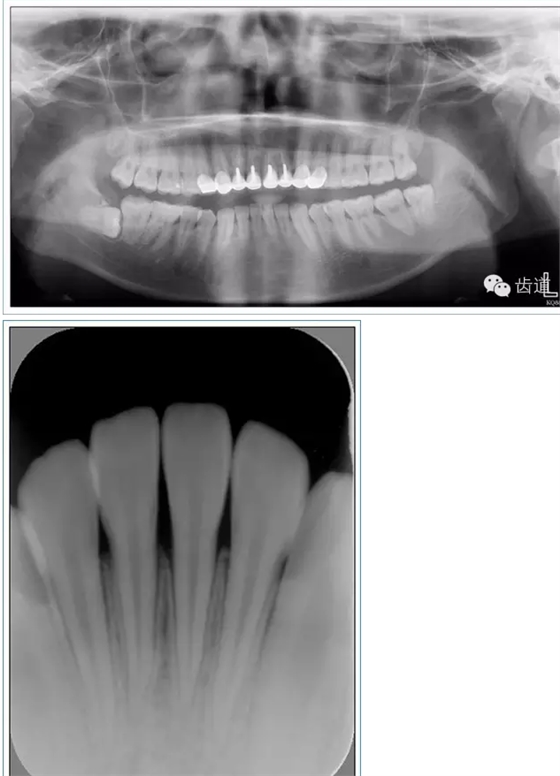

牙體預(yù)備時(shí)應(yīng)考慮的問題

l保護(hù)牙體組織

l基牙具有良好的固位形

l基牙具有良好的抗力形

l預(yù)留修復(fù)體的空間

l邊緣的適合性

l保護(hù)牙周組織

l多個(gè)基牙時(shí)就位道的調(diào)節(jié)

l實(shí)際備牙產(chǎn)生的問題

1. 保護(hù)牙體組織

l防止過度預(yù)備(造成牙髓激惹)

l保留活髓(保留牙體的整體性和韌性)

l過度預(yù)備抗力形喪失